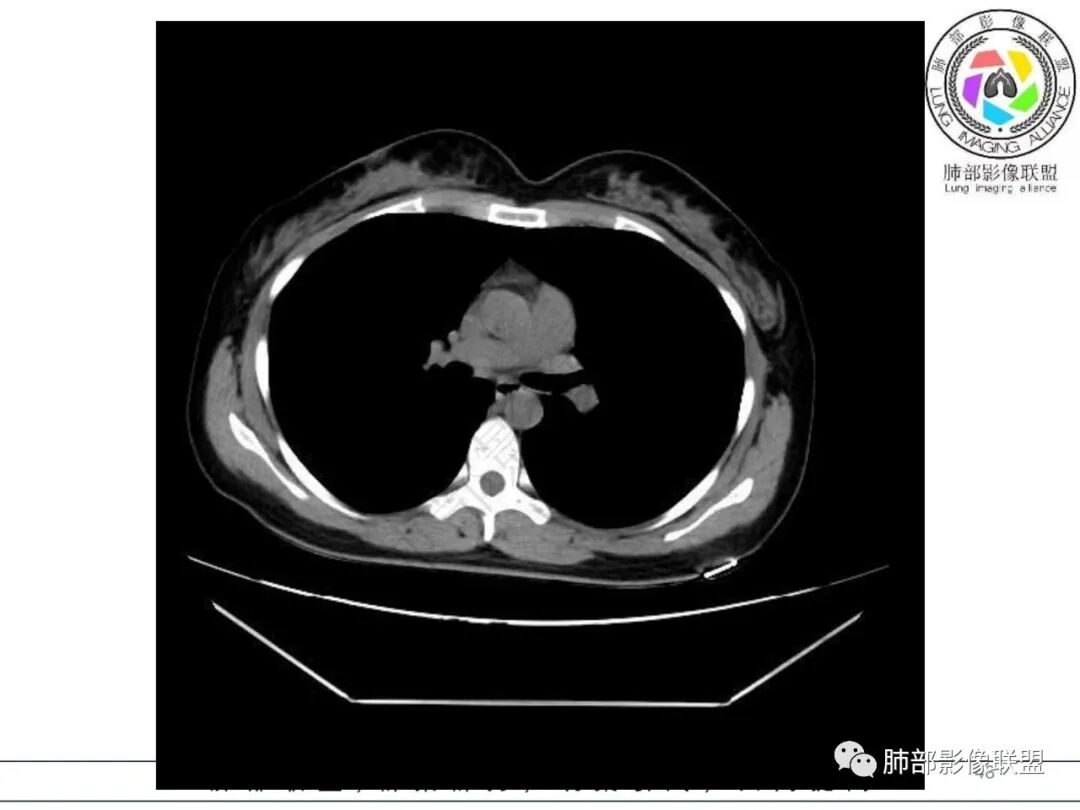

2.影像特征:右肺下叶局限性实变影伴晕征,边界不清,内部支气管尚通畅,实变区密实区边缘稍膨隆。符合炎性病灶特征。

3.综合分析:急性病程,炎性指标高,常见的是普通社区肺炎,如肺炎链球菌感染等。但本例患者临床表现较重,应先表现相对较轻,白细胞不高,须考虑非典型肺炎的可能性。本例隐球菌荚膜实验阴性,而军团菌临床症状一般较重,影像分布也更广泛、进展迅速,多器官损害更明显。因此考虑鹦鹉热衣原体可能性更大一些。其他如腺病毒等感染也是需要排除的。